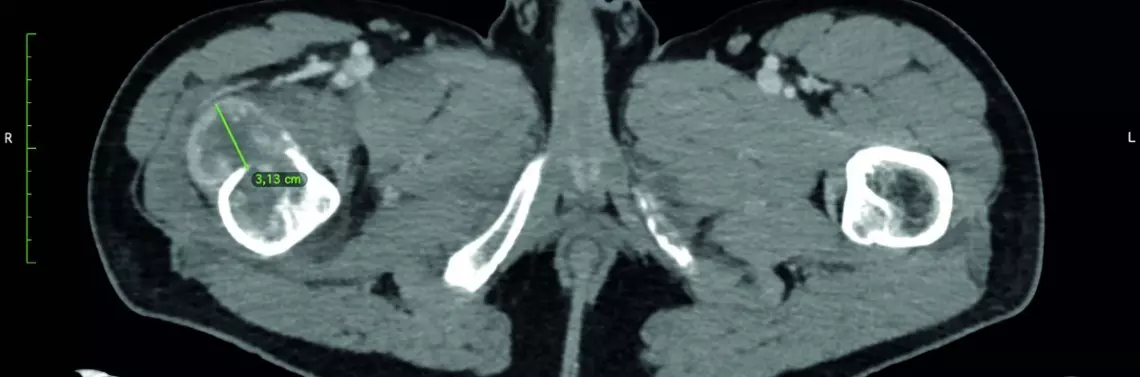

Kolejna operacja w użyciem okularów mieszanej rzeczywistości została wykonana u niespełna 40-letniego pacjenta w przebiegu leczenia raka jasnokomórkowego nerki, u którego doszło do złamania patologicznego bliższego końca kości udowej (ryc. 1).

Podczas przygotowania chorego do resekcji przerzutu i implantacji endoprotezy poresekcyjnej u pacjenta wykonano zabieg embolizacji (ryc. 2A i 2B).